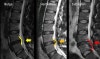

X-ray에서 비특이적인 퇴행성 변화가 보입니다. 4주 이상 지속되는 증상, 심각한 신경학적 증상이나 악화되는 신경학적 장애, 극심한 통증 시에는 병변 확인을 위하여 MRI를 촬영합니다.

MRI : 요추디스크 탈출(Lumbar Herniated Disk)